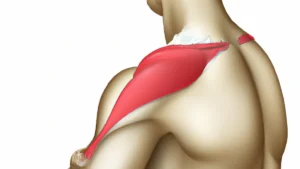

The sacroiliac (SI) joint connects the lower spine to the pelvis. It transfers weight from the upper body to the lower limbs during walking, running, and standing. Inflammation, misalignment, or dysfunction of the SI joint leads to sacroiliac joint dysfunction. Individuals often experience sharp, stabbing pain in the lower back and buttocks, which may radiate down the legs.